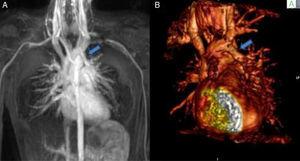

Case reportsCase 1 (partial anomalous venous return with infracardiac drainage)We describe the case of a 14-year-old girl assessed for an incidental finding on chest X-ray (pulmonary asymmetry). The chest X-ray revealed right pulmonary hypoplasia as well as an anomalous pulmonary vein descending below the diaphragm creating a curved shape on the right side, the scimitar sign. Echocardiography showed dextrocardia with apex on the left, at least two pulmonary veins draining into the left atrium, intact atrial and ventricular septa, no dilation of the cardiac chambers, preserved global biventricular systolic function and no signs of pulmonary hypertension. Computed tomography (CT) confirmed and better characterized these imaging findings (Figure 1A). Magnetic resonance imaging (MRI) (Figure 1B), in addition to angiographic evaluation, was also important for excluding associated congenital heart disease, and for assessment of right ventricular (RV) systolic function and volume, as well as left-to-right shunting (Qp:Qs 1:2). Given that the patient was asymptomatic and there was no evidence of cardiac functional impairment, a conservative strategy was adopted.

(A) Coronal-reformatted contrast-enhanced computed tomography showing the scimitar vein draining into the inferior vena cava (arrow) as well as right pulmonary hypoplasia with left lung expansion; (B) sagittal four-dimensional magnetic resonance imaging angiographic image also demonstrating the scimitar vein (orange arrow).